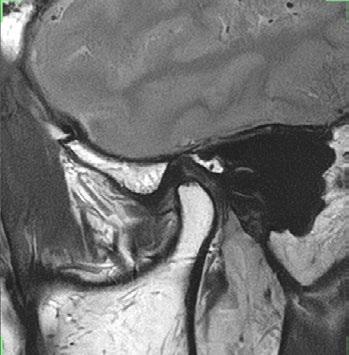

TMJ

16ch Flex SPEEDER, PD, AiCE + Compressed SPEEDER, Res: 0.16 x 0.16 x 2 mm, Scan time: 1:09 min per side.